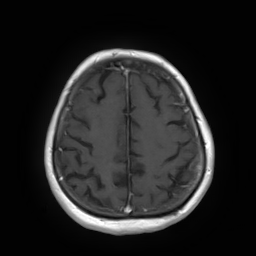

(a) Guide 𝑮𝑮\boldsymbol{G}

Refer to caption

(b) Input 𝑰𝑰\boldsymbol{I}

(c) Guidance map 𝑴𝑴\boldsymbol{M}

(d) Prediction 𝑷𝑷\boldsymbol{P}

(e) Ground truth

Figure 2: Inputs and outputs of the guided filtering pipeline based on the WDSR network. T1 & T2 MRI pairs (a)-(e) and CT & MRI projection images (f)-(j).